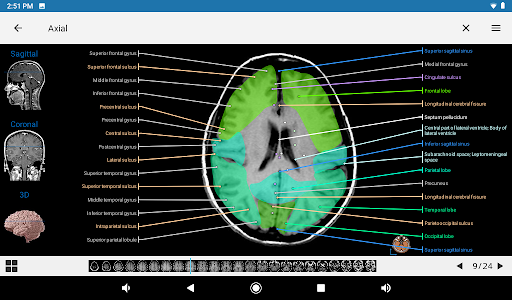

e-Anatomy memiliki lebih dari 26.000 gambar yang berisi serangkaian gambar dalam tampilan aksial, koronal, dan sagital serta radiografi, angiografi, gambar diseksi, bagan anatomi, dan ilustrasi. Semua gambar medis diberi label dengan cermat, lebih dari 967.000 label tersedia dalam 12 bahasa termasuk Terminologia Anatomica Latin.

- Gulir set gambar dengan menyeret jari Anda

- Perbesar dan perkecil

- Ketuk label untuk menampilkan struktur anatomi

- Pilih label anatomi berdasarkan kategori

- Tampilan anatomi sekarang menampilkan lebih banyak label